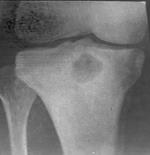

Внутрішньокістковий абс­цес Броді (abscessus Brodie) – обмежений кістковий абсцес, заповне­ний гнійною, кров’янистою або сероз­ною рідиною, яка локалізується часті­ше в метафізі великогомілкової кістки або епіфізі(рис.6).

Рисунок 6. Рентгенограма внутрішньокісткового абсцесу Броді.

Захворювання починаєть­ся в молодому віці і може себе прояви­ти через багато років. Пацієнти скаржать­ся на ниючий біль у кінцівці, який по­силюється вночі або під час фізичного навантаження, локальну болючість під час постукування по ураженій ділянці. Діагноз ставлять на підставі рентгено­логічних даних. У кістці виявляється круглої форми різних розмірів порож­нина з чіткими контурами. По краях порожнини є склеротична облямівка. Температурна реакція відсутня. Ліку­вання оперативне: розкриття порож­нини абсцесу, вишкрібання її, проми­вання антибіотиками і тампонада м’я­зовим клаптем на ніжці.